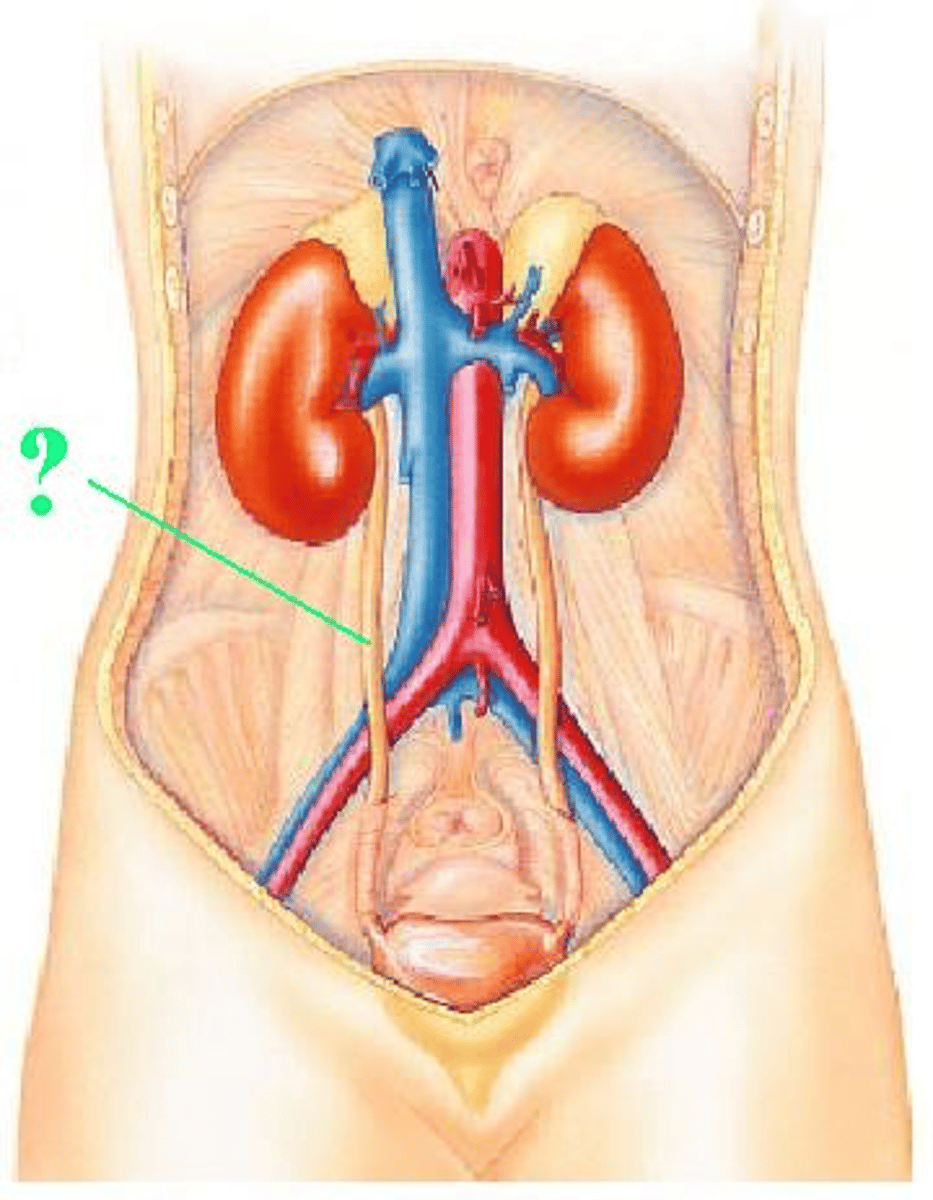

ureter

Identify the indicated structure.